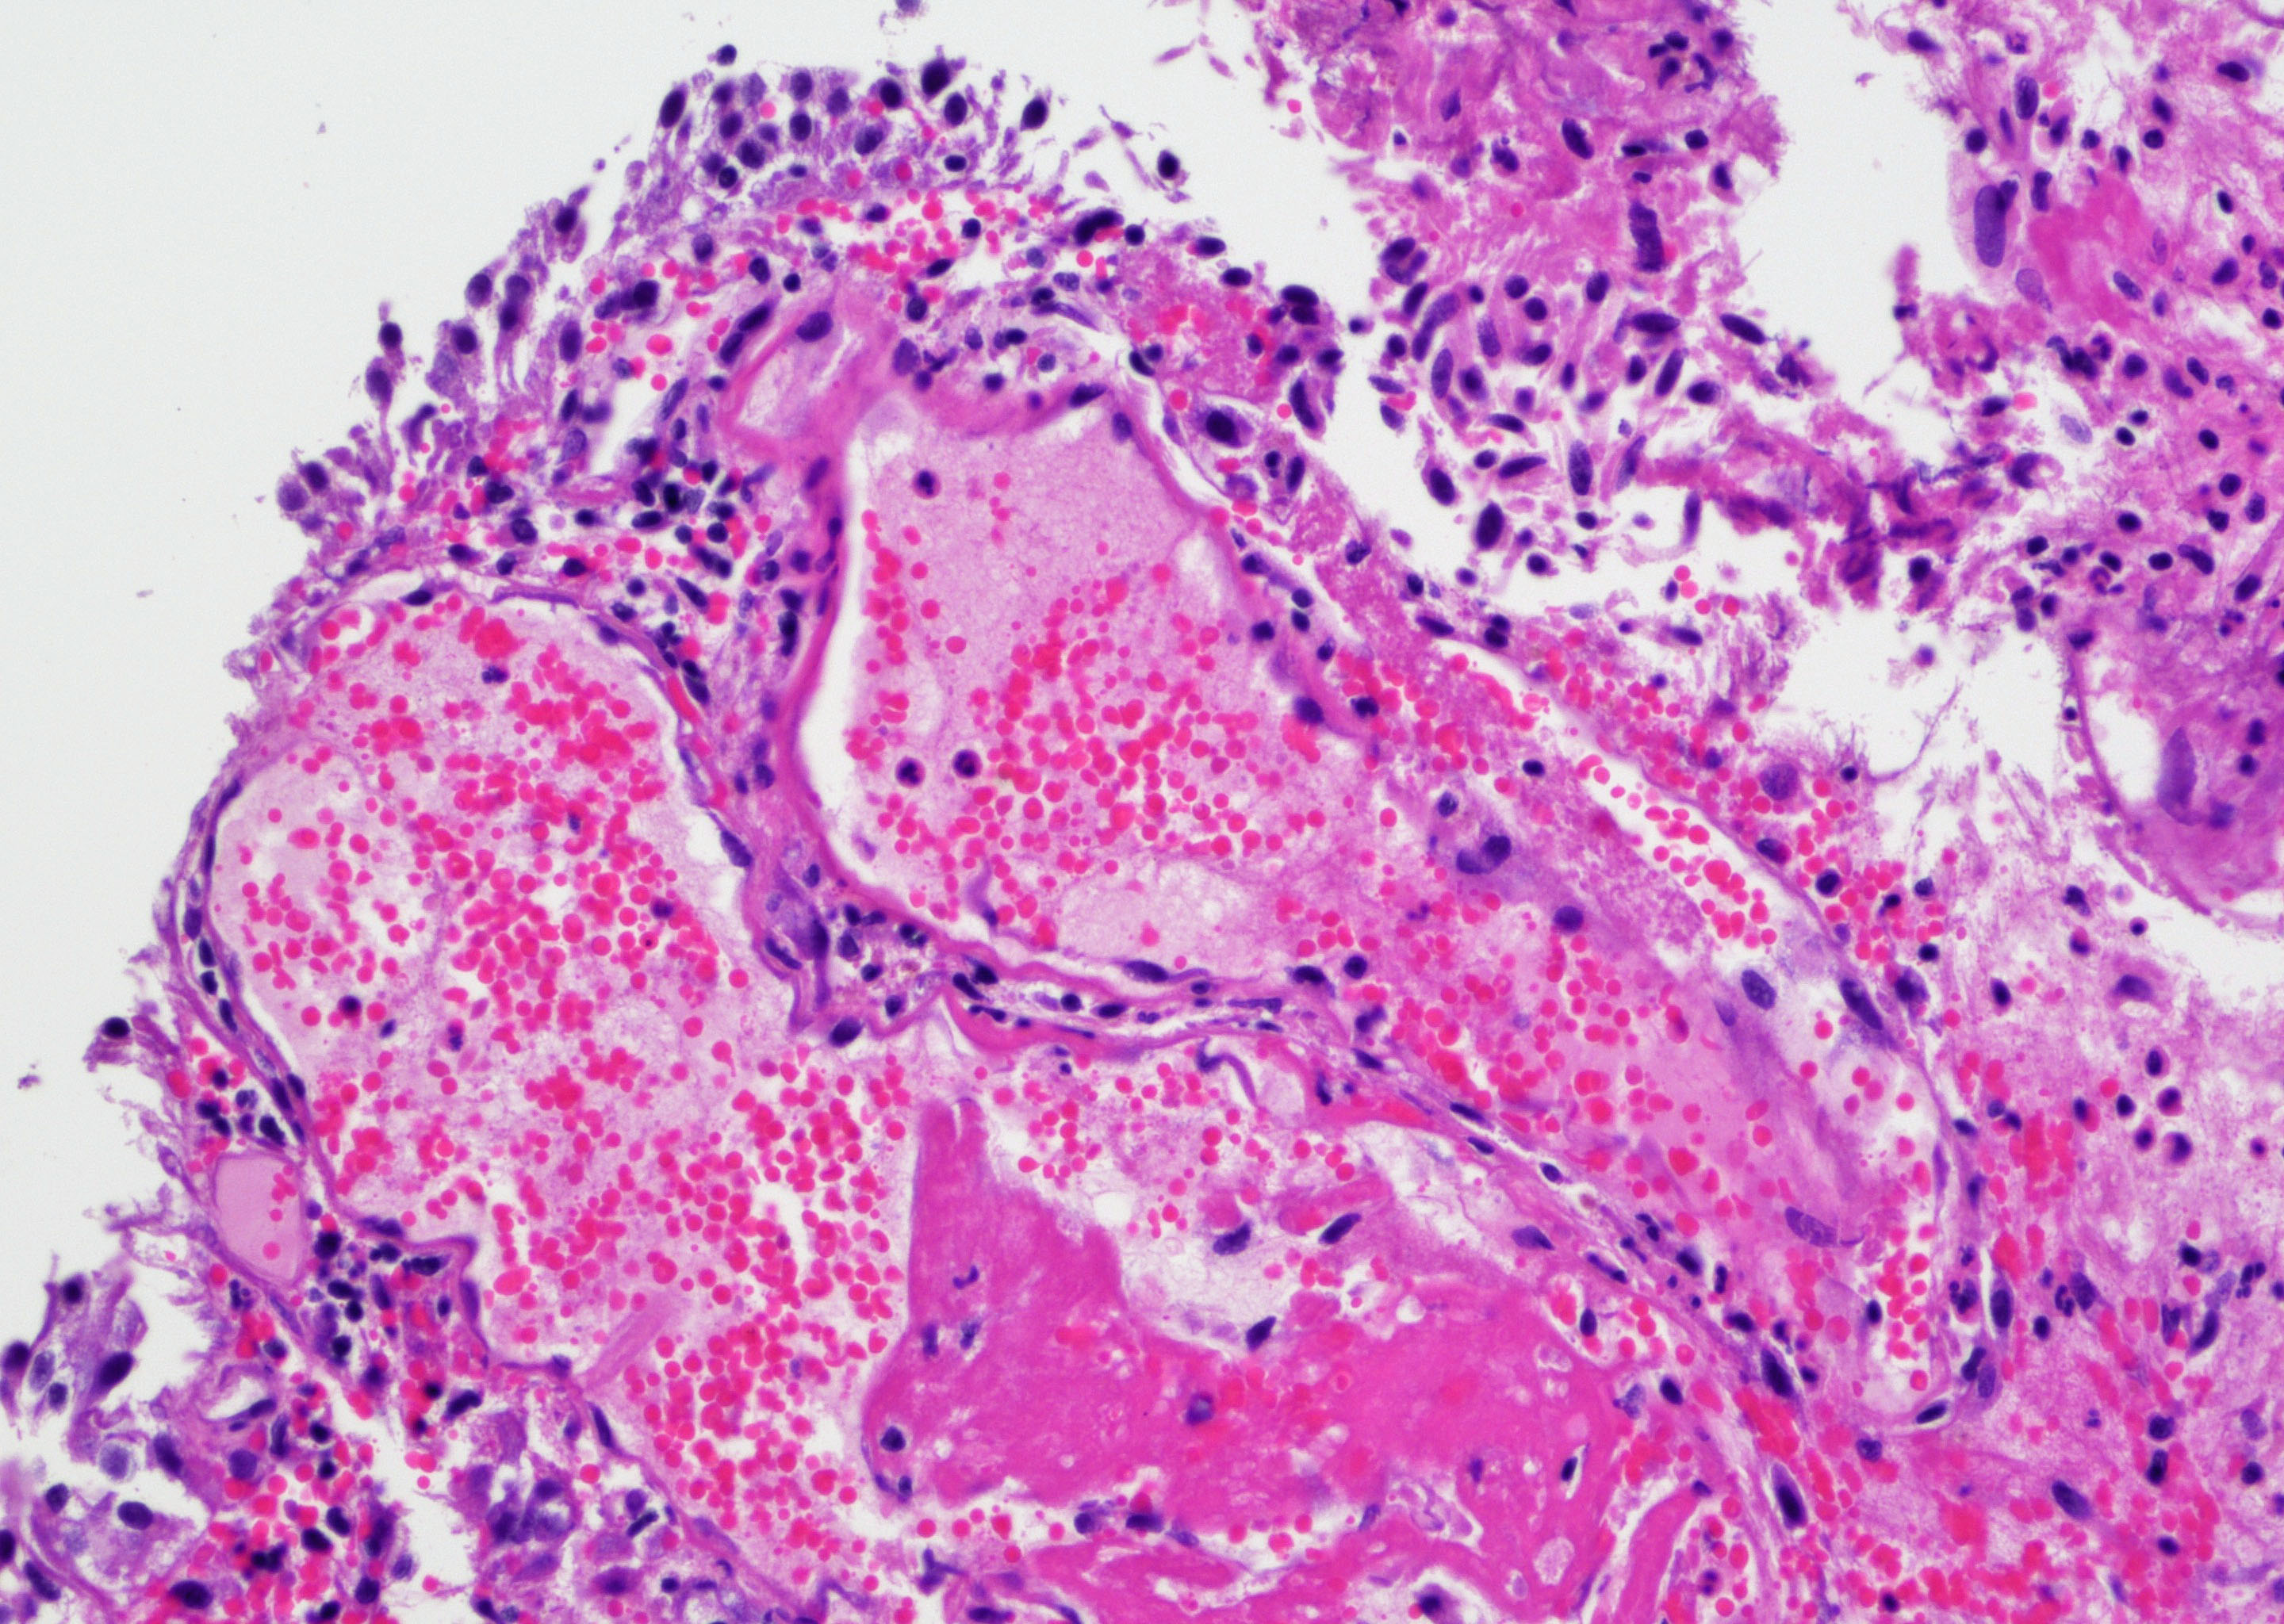

- Vessels with fibrin thrombi, fibrinoid vascular necrosis, vascular congestion, thickened walls, endothelial proliferation and telangiectasia

- Acute and chronic inflammation

- Fibrosis and edema

- Hemorrhage and hemosiderin

- Pseudocarcinomatous urothelial hyperplasia: variable sized urothelial cords and nests with rounded or irregular edges present in the lamina propria and enclose dilated blood vessels with fibrin deposition (Am J Surg Pathol 2008;32:92)

- Acute phase: edematous, congested and telangiectatic vessels, acute and chronic inflammatory infiltrate, atypical stromal cells with multinucleated forms

- Chronic phase: atrophic urothelium, atrophic smooth muscle layer, collagen deposition (fibrosis) (Am J Surg Pathol 2004;28:909)

Microscopic (histologic) images

Contributed by Y. Albert Yeh, M.D., Ph.D. and Jennifer Lee, M.D.

- Comment: There is a history of radiation therapy per the medical record. The transurethral resection of the bladder lesion shows fragments of urothelial mucosa with total and partial denudation of urothelium. The urothelial lining cells show reactive changes. There is marked edema, hemorrhage and mixed inflammatory infiltrate composed predominantly of neutrophils and lymphocytes in the lamina propria. Reactive multinucleated stromal fibroblasts are seen. Telangiectatic vessels with fibrinoid necrosis and intravascular fibrin deposition are seen. Anastomosing cords and nests of urothelial cells encircling the vessels with fibrin deposition is evident. Urothelial cells with hyperchromatic nuclei, increased nuclear to cytoplasmic ratio and prominent nucleoli are seen. These features are consistent with radiation cystitis with pseudocarcinomatous urothelial hyperplasia. Muscularis propria is not identified in this specimen.

A 68 year old man presented with hematuria and dysuria. He has a medical history of prostate cancer that was treated with radiation therapy. Cystoscopy revealed hemorrhage in the right bladder wall. A transurethral resection of the lesion was performed. A photomicrograph is shown above. What is the diagnosis?

- Radiation cystitis with pseudocarcinomatous hyperplasia

C. Radiation cystitis with pseudocarcinomatous hyperplasia. Answers A, B and D are incorrect because anastomosing cords and nests of urothelial cells encircling ectatic vessels with intravascular and stromal fibrin deposition in a background of mixed inflammation are not present in these entities.